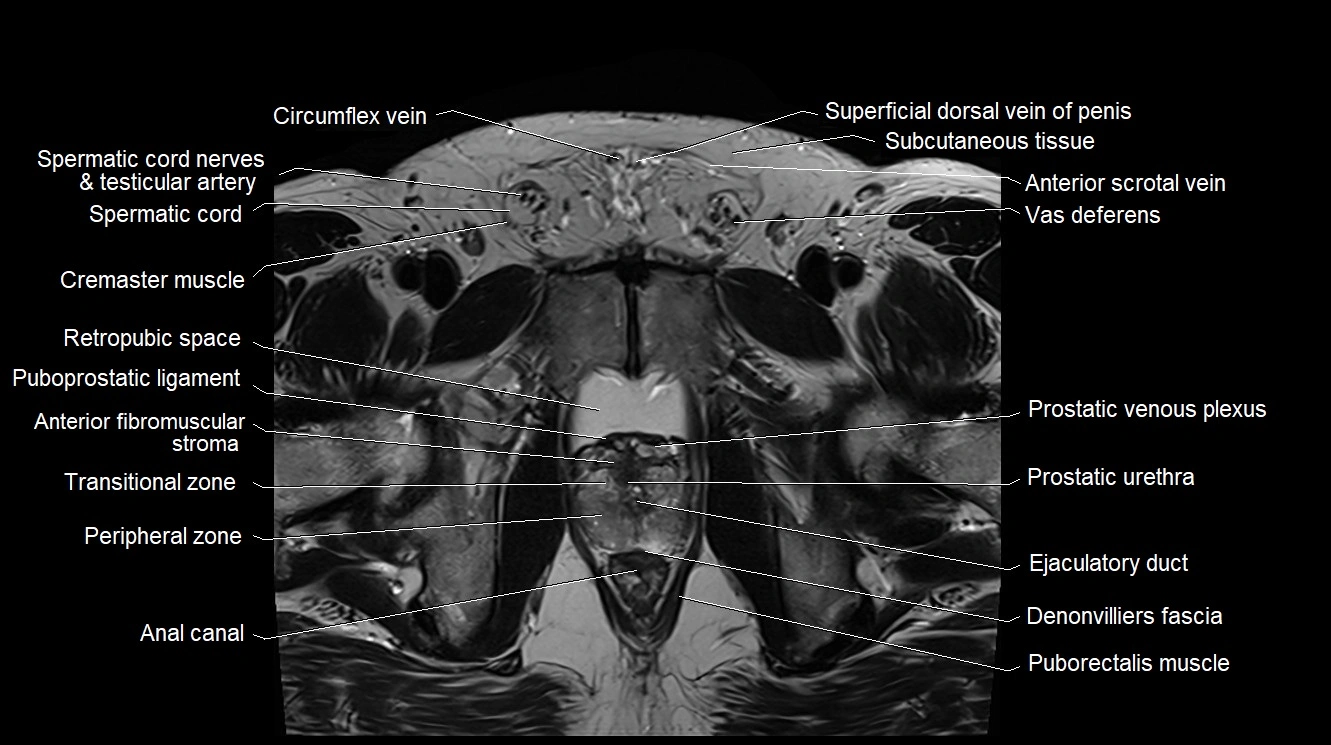

MRI image